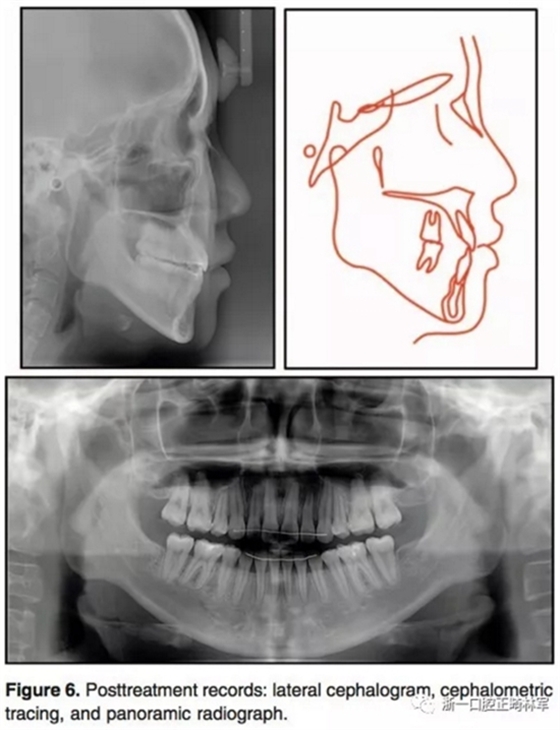

治療后結(jié)果示,治療目標(biāo)達(dá)成。側(cè)貌改善。唇可以完全閉合,獲得了美學(xué)微笑(圖5)。全景示間隙關(guān)閉,牙根平行度可,未見(jiàn)明顯吸收。側(cè)位片分析和重疊像分析示上前后牙分別壓入2.8mm和1.9mm。下前后牙分別壓入4.2mm和1.4mm。上下頜前牙用最大支抗內(nèi)收。雙牙弓壓入后,下頜發(fā)生了逆時(shí)針旋轉(zhuǎn)(2.1°)??和頦前點(diǎn)前移(3mm)。